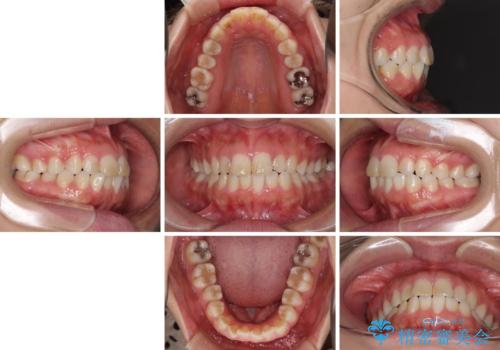

- ワイヤーではない矯正治療があると聞いたとのことで来院された患者様です。

長年前歯のデコボコを気にしていたもののワイヤー矯正に抵抗があり躊躇していたそうですが、インビザラインなら治療してみたいとのことで相談にいらっしゃいました。

インビザライン適用の歯列であったため、歯と歯の間を削るIPRを用いて改善することとしました。

お仕事柄、長時間のマウスピース装着が苦ではなかったので、歯列はすぐに整いましたが、ゆっくりとした交換頻度であったので、2年ほどの治療期間を要しました。